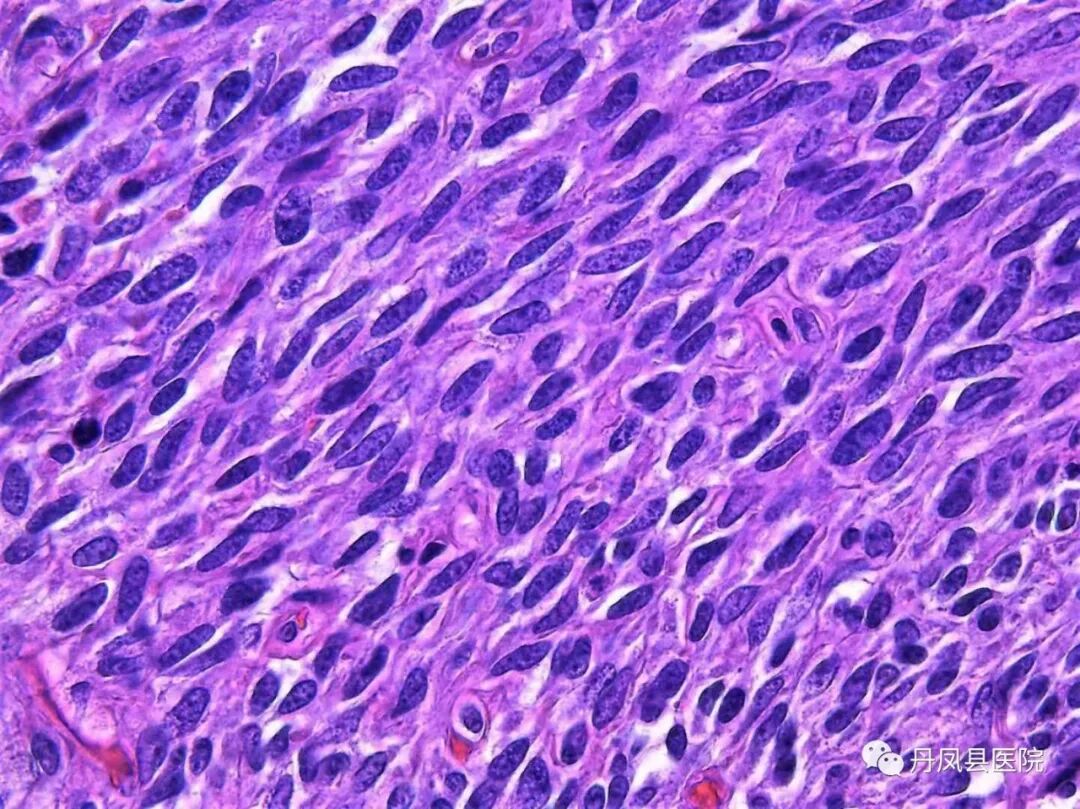

医界先导W.Dsler教授曾说过“病理乃医学之本”。病理主要是用显微镜观察人体组织细胞变化,必要时结合相关特殊染色作出疾病诊断,是临床医师确定患者临床诊断、治疗方案和评估预后的重要依据,因此在业界,病理科医生也被称为“医生的医生”。

科室风采丹凤县医院病理科成立于1980年5月,是丹凤县域内技术力量最雄厚、规模及病检量最大的病理科,承担全县大部分的临床病理、细胞学检查及病理科教研工作。科室现有工作人员5名,其中主治医师3名,技术员2名。科室人员曾先后到西安交通大学第一附属医院、西安交通大学第二附属医院进修学习,并与多家上级医院病理科保持合作医疗关系。

主治医师,病理科主任,商洛市医学会病理专业委员会委员,商洛市抗癌协会肿瘤微创介入专业委员会委员,从事病理专业工作17年,曾赴西安交通大学第一附属医院进行学习,多次参加病理专业知识学习培训班,对各种常见病、多发病的病理诊断有着丰富的经验,特别对消化道肿瘤、宫颈肿瘤的早期病变和皮肤病变及软组织肿瘤的病理诊断有着深入的研究。科室地址